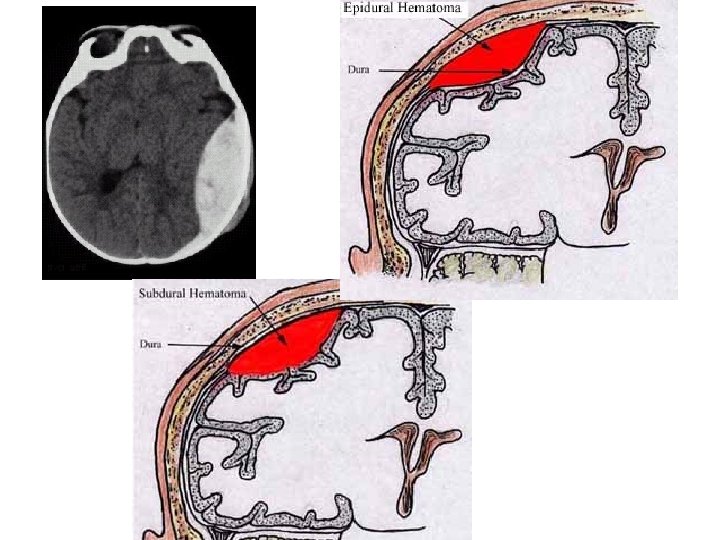

C) Meninges Three membranes that surround and suspends the brain and spinal chord. Used for shock absorption, cushioning and to dispense force 1) Dura Mater 2) Arachnoid Mater- silk like threads Sub-arachnoid space~ where spinal fluid is found (CSF- cerebral spinal fluid) 3) Pia Mater

II. Injuries cont. • 3) Hematoma • Blood/lymph in a localized area- usually no room • If happens in skull there is no room so blood puts pressure in brain- neurological disfunction • Named by where blood is located: Epidural Subdural

II. Injuries cont • 1) Epidural Hematoma- 1 st LOC then headache, vomitting, dilated pupils, etc • TX-immediate surgery • 2) Subdural Hematoma- Signs might not show up for days/weeks- slow bleed from vein fatal